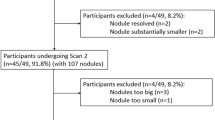

Segmentation accuracy

The number of nodules that were segmented adequately by each individual package varied significantly from between 71% and 86% before manual correction and between 71% and 98% after correction depending on the software package used (p < 0.001) (Fig. 3).

Comparison of visual rating of segmentation accuracy for the various software packages. The graph displays the percentage of nodules for which segmentation was rated “excellent” and/or “satisfactory” on scan 1 and scan 2. Nodules for which segmentation was rated “poor” or “failure” on at least one of the scans are summarized as “inadequately” segmented nodules. a: Displays the raw results without manual adjustment of nodule contours, while (b) displays results after manual correction of the segmentation. Note that systems A and E did not allow for manual correction